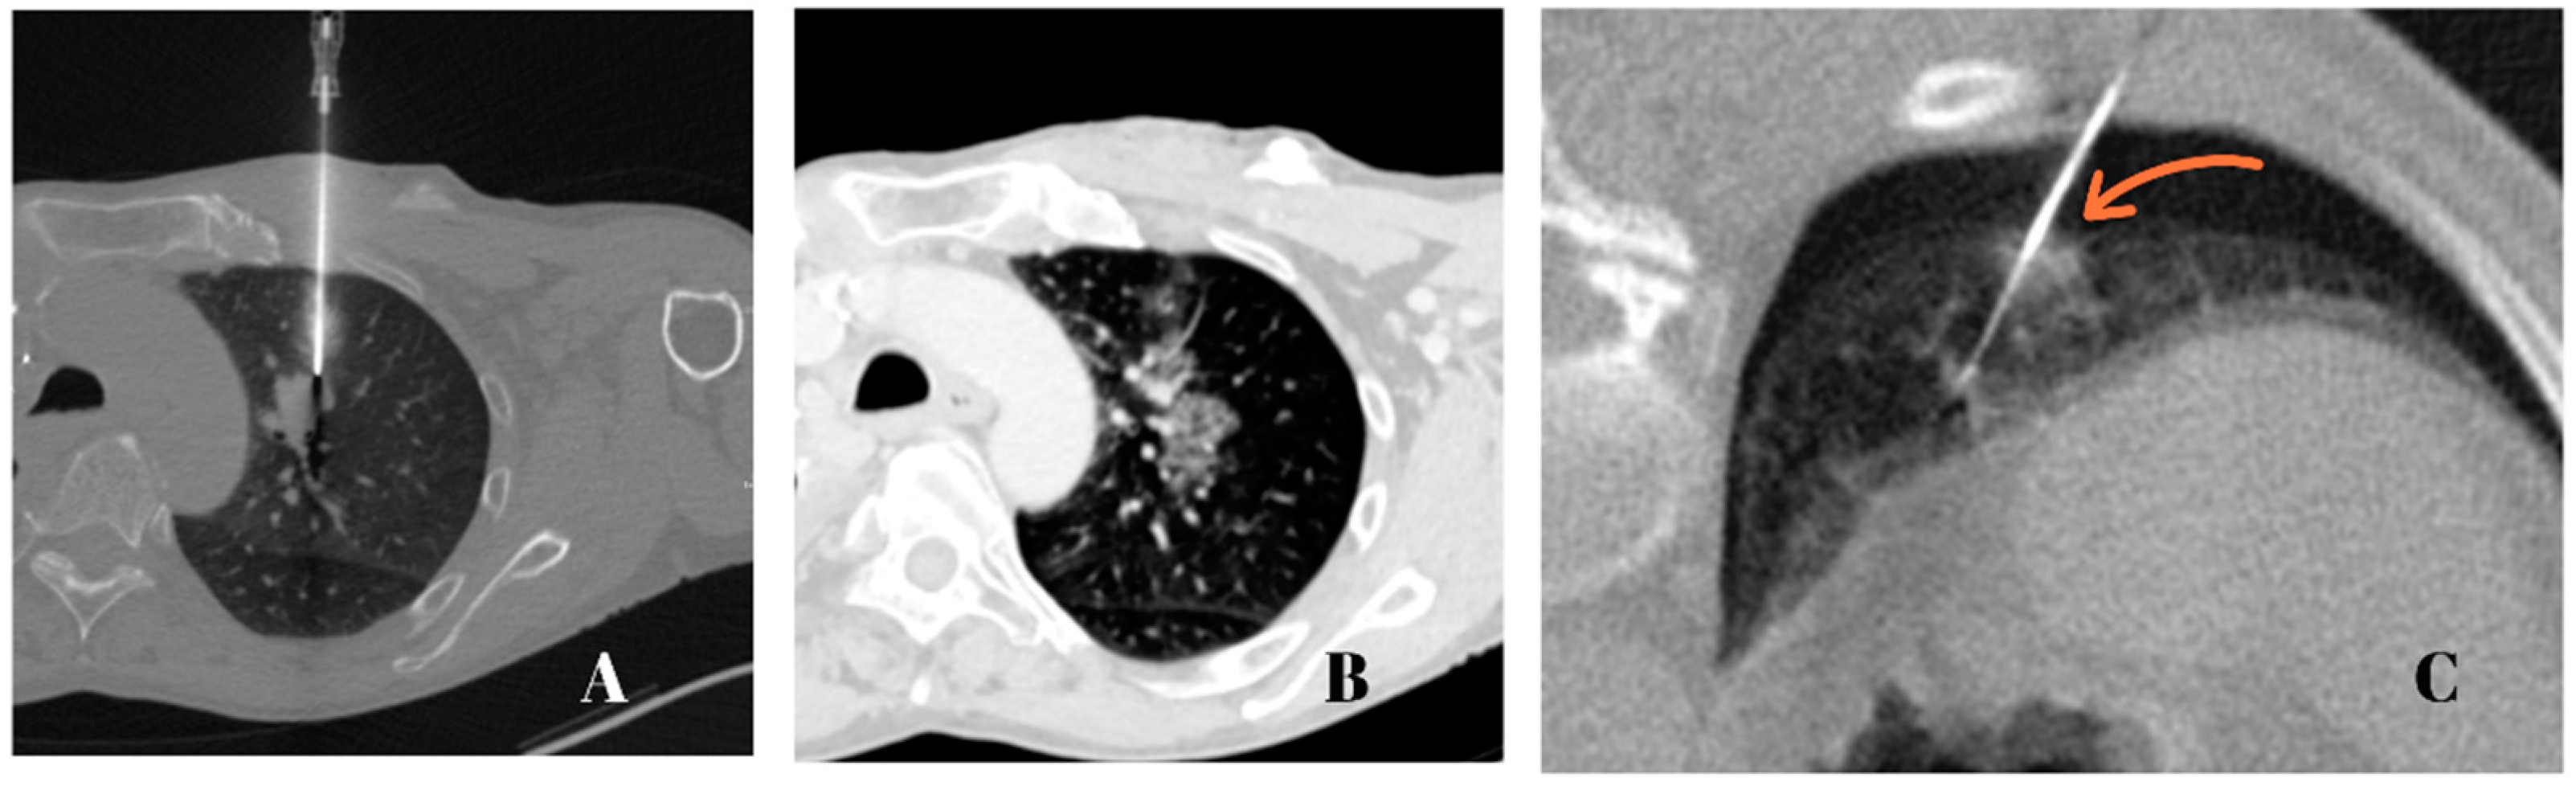

2. Materials and Methods

2.4. Biopsy Protocol

2.5. Measurement Yield